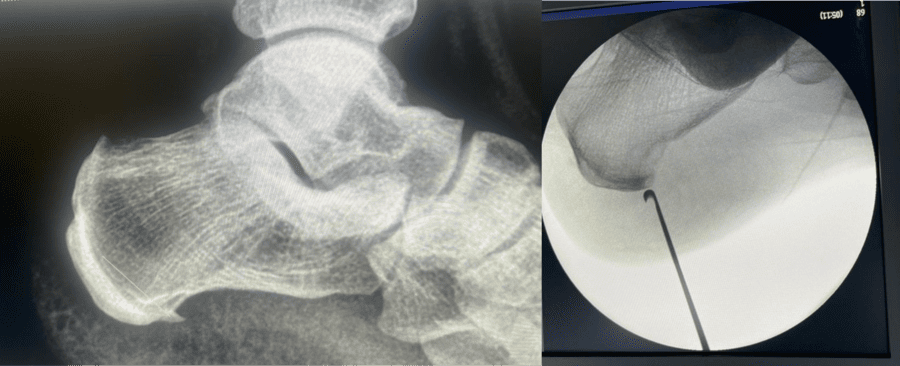

Fascitis Plantar / Espolón Calcáneo

La fascitis plantar es una de las causas más comunes de dolor en el talón. Se produce por la inflamación de la fascia plantar, una banda gruesa de tejido que recorre la planta del pie, desde el talón hasta los dedos, y que soporta el arco del pie. El espolón calcáneo es un crecimiento óseo que a veces se forma en el hueso del talón (calcáneo) en respuesta a la tensión crónica sobre la fascia plantar, aunque el espolón en sí mismo no siempre es la causa directa del dolor.

Diagnóstico: El diagnóstico es principalmente clínico, basado en los síntomas y el examen físico.

- Radiografías: Se pueden realizar para confirmar la presencia de un espolón calcáneo (si es que existe) y para descartar otras causas de dolor en el talón, como fracturas por estrés.

Tratamiento: El tratamiento es principalmente conservador y suele ser muy efectivo.

- Ondas de choque: En casos de dolor crónico que no responde a otras terapias.